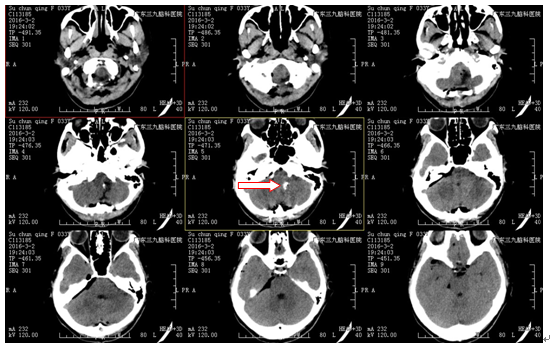

苏女士,33岁,因“头晕半年”入院。半年前无明显诱因出现头晕,程度中等,以头仰位后明显,无头痛、恶心、呕吐及肢体抽搐,由于不影响正常生活,一直未予特别处理,近期出现头晕较前略加重,遂到当地医院就诊,行头颅CT提示脑干占位性病变,未予处理。现为求进一步诊治,来我院就诊,门诊拟“枕骨大孔区占位性病变”收治入院。病后精神、睡眠良好,胃纳正常,大小便正常。头颅MR提示脑干占位性病变。

诊断:脑干占位性病变,考虑低级别胶质瘤可能性大

治疗:入院后完善术前准备,于2016-3-2行脑干占位性病变切除术,术中见脑干延髓区肿瘤,向左外侧生长,血供一般,边界欠清,大部分钙化明显。给予镜下大部分切除肿瘤,术后给予抗炎、营养神经等对症治疗,予预防感染、止血、营养神经等康复治疗,术后病理检查提示:毛细胞星形细胞瘤(WHOI级)。